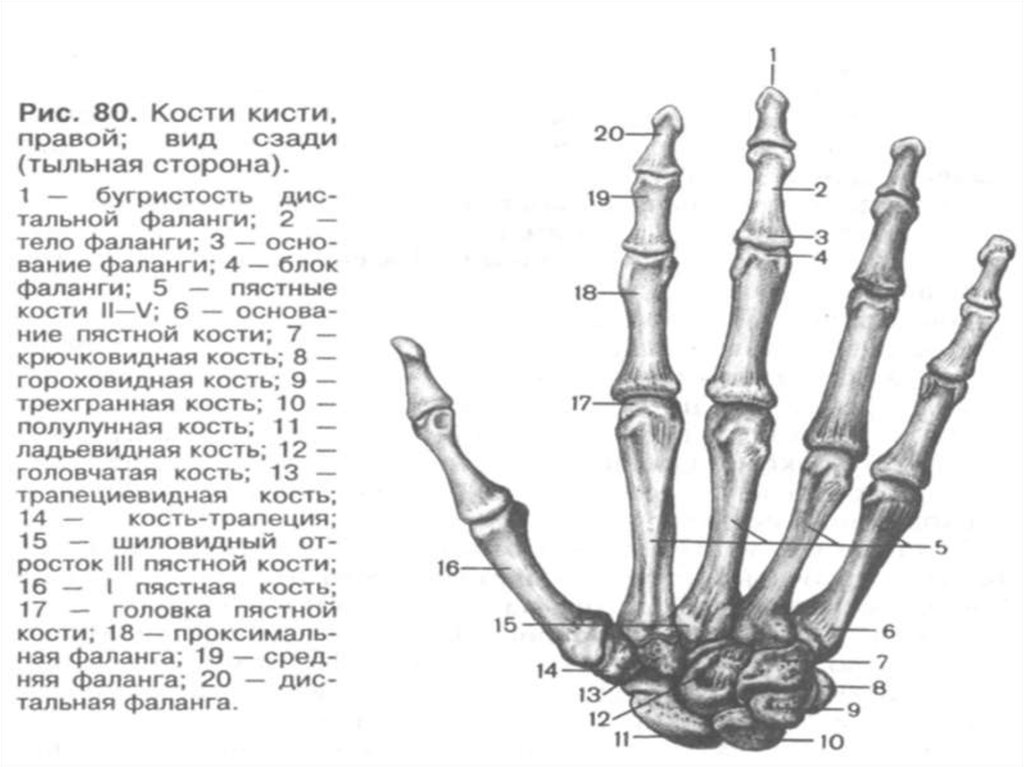

Анатомия кисти руки и строение костей